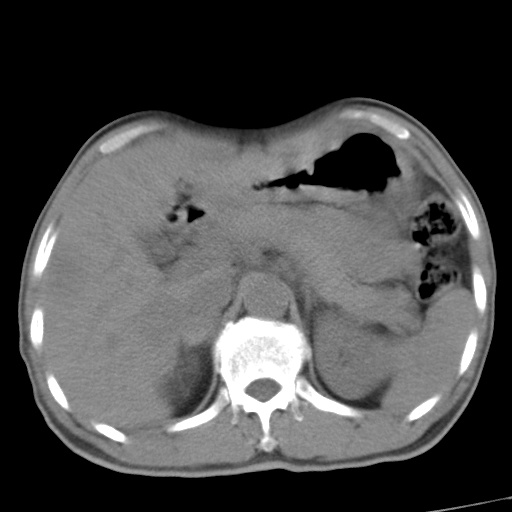

标题: CT17975:请求会诊。男、57岁。上腹部胀痛2天。临床诊断:糜 [打印本页]

标题: CT17975:请求会诊。男、57岁。上腹部胀痛2天。临床诊断:糜

肝脏多发类圆形低密度影,考虑肝脏转移瘤,肝胃韧带一淋巴结肿大,原发?胃癌?

考虑胃癌并肝脏及腹膜后淋巴结转移;不排除淋巴瘤。

肝内转移瘤,腹腔及腹膜后淋巴结转移。